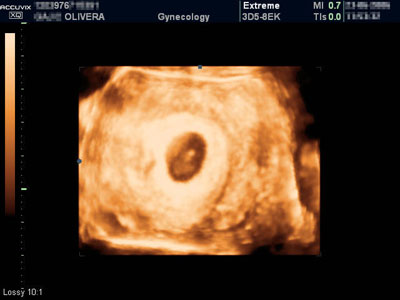

• www.4dordinacija.com ŠTA JE 4D ULTRAZVUK? Ultrazvuk koji nudi četvorodimenzionalan prikaz ploda. Šta to zapravo znači? Direktan uvid u dešavanja u majčinom stomaku tj. „live“ (uživo) prikaz izgleda i ponašanja ploda. Dakle, 4D je najsavremeniji prozor u bebin svet. ZAŠTO 4D? Zato što nudi mnogo više od samo „lepe slike“. Višestruko povećava mogućnost potvrđivanja normalnosti razvoja ploda u rizičnoj trudnoći, kao i rano otkrivanje neočekivanih abnormalnosti ploda. Lice, šake i stopala, česte su mete pojave izolovanih neočekivanih abnormalnosti (koje mogu i ne moraju biti genski uslovljene). Njihov fascinantan prikaz pri 4D pregledu ne dozvoljava propust, što ovaj pregled čini superiornim u odnosu na dosadašnje tradicionalne preglede. Dakle, 4D ultrazvuk obezbeđuje novu dimenziju infor...